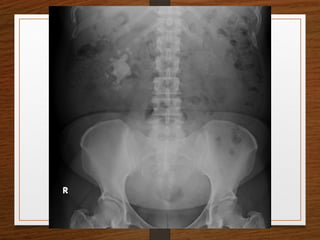

What are the D/D of a radiopaque shadow in this region?

• Kidney stone

• Gallstones

• Pancreatic calculi

• Foreign body

• Fecolith

• Phleboliths

• calcified lymph node

• calcified renal tuberculosis

• calcified adrenal gland

• chip fracture of a transverse process of vertebra or calcification of costal

cartilage